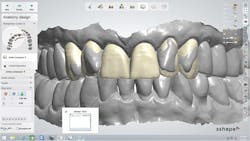

The laboratory technician worked with the color turned off to perform the restorative design quickly while the patient watched. The goal was to increase the length of the central incisors, bring them further labially, and reduce the labial position of the two lateral incisors (figure 4). Only minor changes were planned for the canines.

Figure 4: The goal of the digitally designed treatment plan was to increase the length of the central incisors, bring them further labially, and reduce the labial position of the two lateral incisors, with only minor changes planned for the canines.

When the color was turned back on, the patient easily viewed and understood the 3-D digital diagnostic plan, which involved placing lithium disilicate (IPS e.max CAD, Ivoclar

Vivadent) crowns on teeth Nos. 6 through 11 (figure 5). The treatment goals were explained in a very efficient and effective manner, and understood by the patient. Major potential complications and the possibility of pulp exposure during tooth preparation of both laterals were also explained, after which the patient accepted the treatment plan and scheduled the first clinical appointment.

Figure 5: With the color turned back on, the patient easily understood the 3-D digital diagnostic plan.